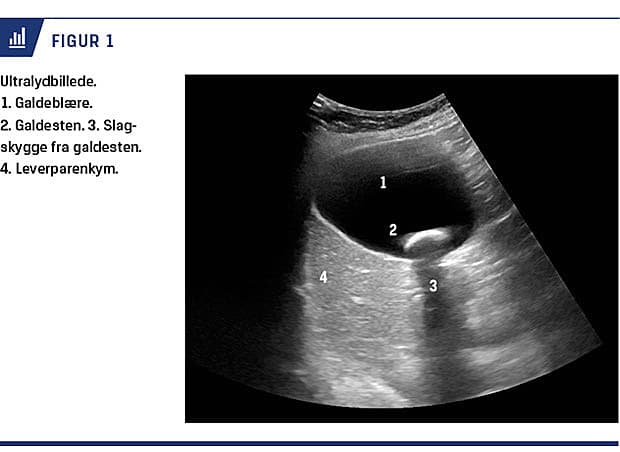

Galdeblæresten (galdesten) (Figur 1) er hyppigt forekommende, oftest asymptomatiske og giver kun sjældent årsag til komplikationer [1- 4]. Det er uklart,

hvorfor der i Danmark foretages et stigende antal kolecystektomier (i 2002 ca. 3.000 operationer [5, 6], i 2014 ca. 6.000 operationer if. Landspatientregistret). Symptomatisk ukompliceret galdestensygdom defineres i det følgende som galdestensygdom.